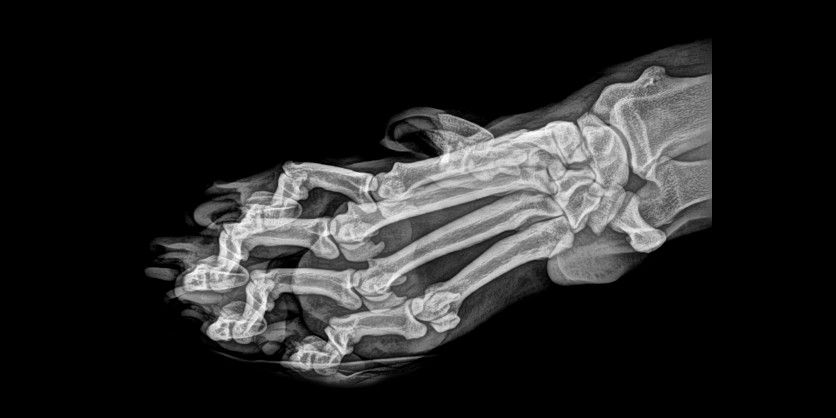

Desde su descubrimiento en 1895 por parte del profesor alemán Wilhelm Röntgen los rayos X han jugado un papel fundamental en las sociedades humanas. Son usados en campos tan distintos como el sanitario, la seguridad en el transporte e incluso la identificación de obras de arte. Su utilización está tan extendida que a veces deja imágenes tan curiosas como las recogidas en esta galería.